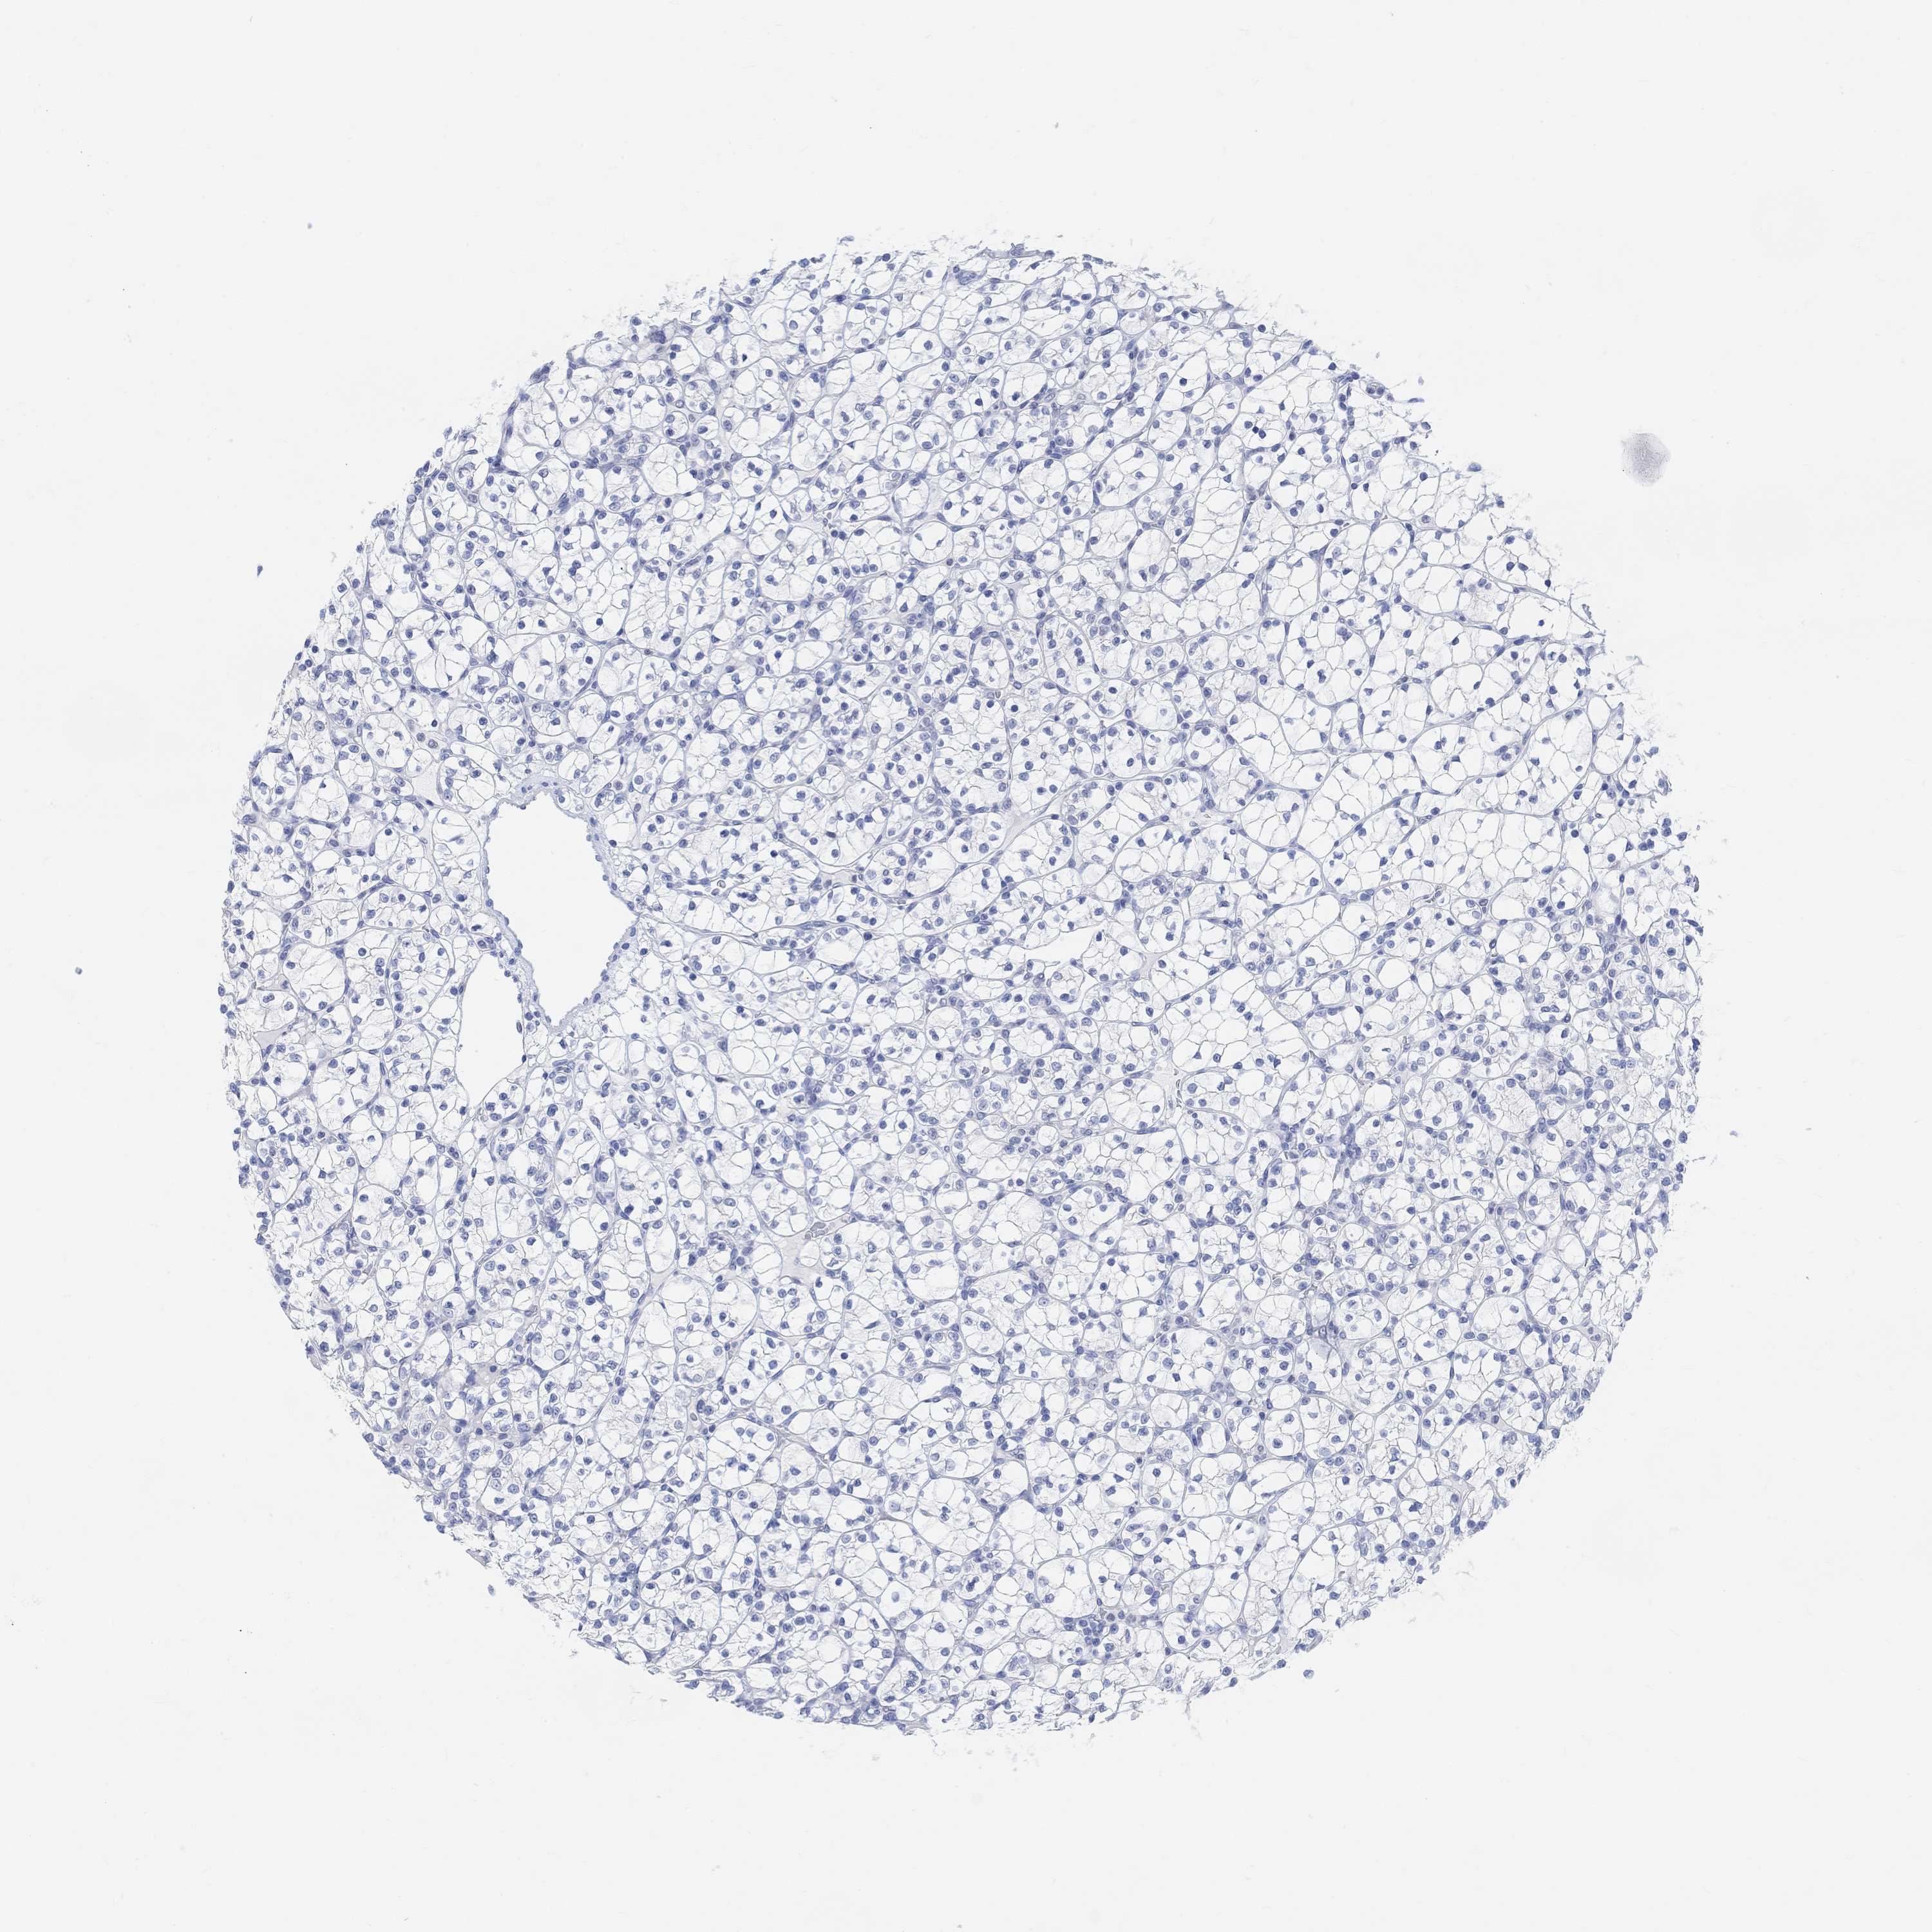

CANCER RENAL CANCER Show tissue menu

KICH TCGA KIRC TCGA KIRC VALIDATION KIRP TCGA PROTEIN RCC CPTAC PROTEIN EXPRESSION